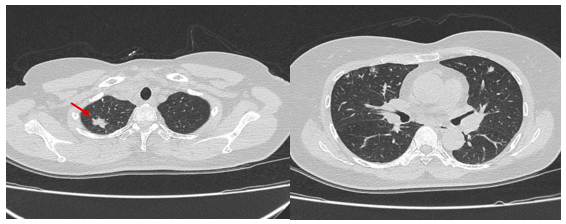

- Chụp cắt lớp vi tính lồng ngực: Nhu mô thùy trên phổi (Phải) có nốt tổn thương kích thước 13x14mm,bờ không đều, ngấm thuốc, sau tiêm. Rải rác nốt đặc 2 bên thùy phổi kích thước 3-10mm. Trung thất các nhóm 1R; 2R; 4R; 5; 8; 10RL có vài hạch lớn nhất kích thước 26x15mm; bờ không đều; ngấm thuốc không đồng nhất sau tiêm. Thượng đòn 2 bên có vài hạch tính chất tương tự; hạch bên phải kích thước 11x14mm

Hình 3: Hình ảnh cắt lớp vi tính ngực có tiêm: Trung thất các nhóm 1R; 2R; 4R; 5; 8; 10RL có vài hạch lớn nhất kích thước 26x15mm; bờ không đều; ngấm thuốc không đồng nhất sau tiêm (mũi tên màu cam)